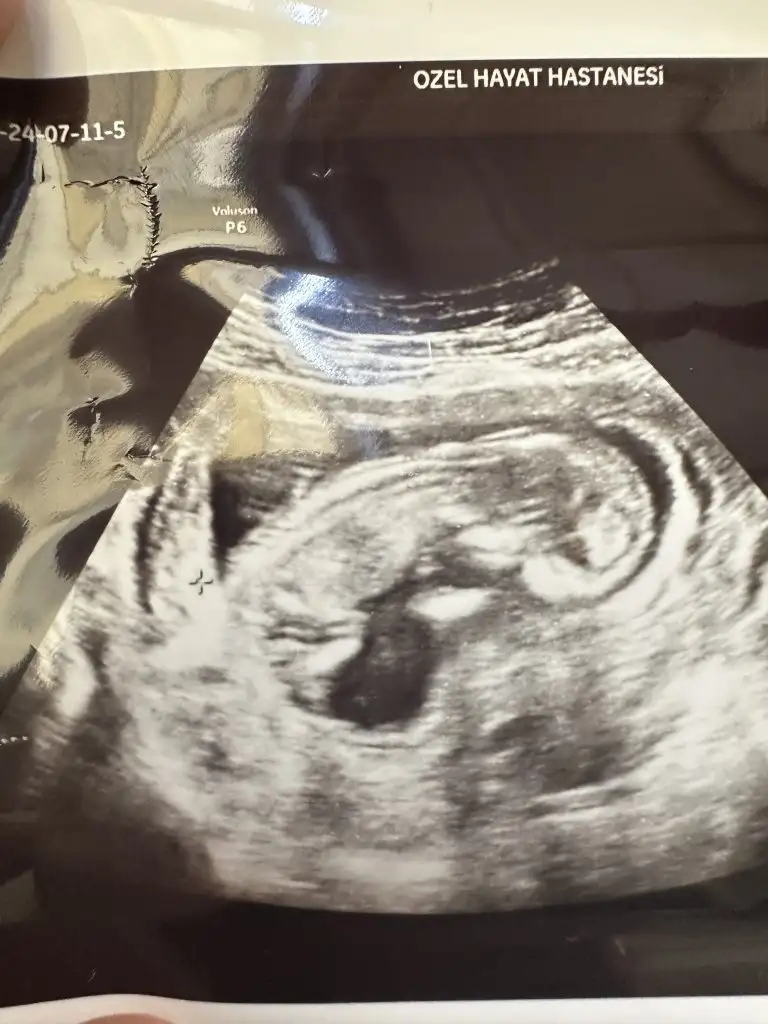

12 haftalık cinsiyeti belli oldu

Merhaba biz de 12 haftalığız ultrason resim çok benzettim benim bebeğime bize doktor yanılma payım yüksek emin değilim sadece tahmin kıza benziyor dedi sizce bakar mısınız kız mı erkek mi bana hiç kız gibi gelmiyor erkek gibi geliyor

Kızlar dün doktorum cinsiyet tahmini yaptı kız büyük ihtimal ama 3 hafta sonra tekrar bakarız kesin o zaman belli olur dedi ben hep erkek hissediyordum ama kız olunca çok mutlu oldum hissiyat olarak sadece erkek olucak kesin diyordum ama yanıldım sanırım sizce cinsiyeti değişicek mi çok heycanlıyım ☺️ Ultrason fotoğrafını asağıya ekliyorum Eki Görüntüle 3233482